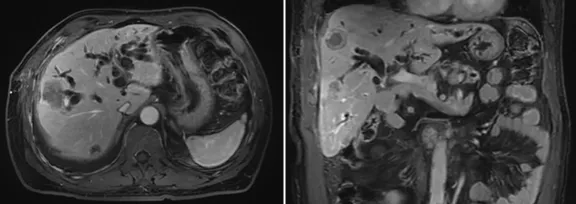

6月復查,上腹部MRI提示考慮肝內多發轉移,行標準治療,予全身化療;

壺腹部腺癌術后改變,左右肝管匯合部異常信號,不除外復發可能;考慮肝內多發轉移瘤形成